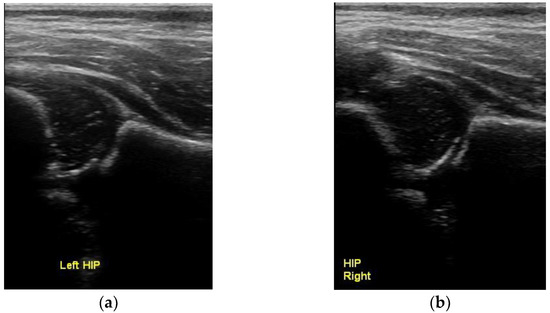

Concentric Circles: A New Ultrasonographic Sign for the Diagnosis of Normal Infantile Hip Development

5. Conclusions